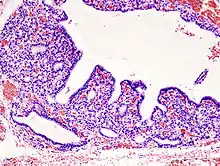

• Hyperplasia: Increase in organ size/tissue mass by increase in cell count.

Hyperplasia of the thyorid follicles in hyperthyroidism, H&E staining.